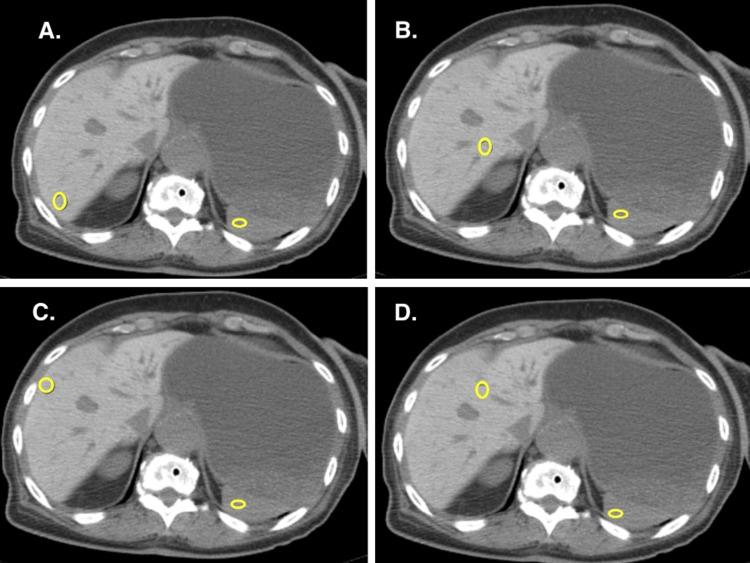

Amiodarone, a class III antiarrhythmic drug, is commonly used for the management of life-threatening ventricular arrhythmias, atrial fibrillation, and other refractory supra-ventricular arrhythmias. Factors like a large volume of distribution, lipophilic property, deposition in tissues in large amounts, etc. have led to the development of amiodarone-induced multisystem adverse events. We report a case of amiodarone-induced hepatic attenuation on computed tomography (CT) of the abdomen in an elderly female patient. Amiodarone with a composition of 40% iodine by weight deposits in the liver, leading to characteristically increased radiodensity reported as increased attenuation on CT scan. Surprisingly, the severity and extent of hepatic attenuation on CT scans do not necessarily correlate with the total exposure to amiodarone over time. Individual factors may influence the liver's response to the drug, leading to varying degrees of hepatic changes. To minimize the risk of adverse events associated with amiodarone, clinicians should carefully adjust the dosage to the lowest effective level and regularly monitor liver function tests in patients. This proactive approach enables early detection of liver dysfunction and facilitates timely adjustments or discontinuation of amiodarone, thereby reducing potential harm.

胺碘酮是一种Ⅲ类抗心律失常药物,常用于治疗危及生命的室性心律失常、心房颤动及其他难治性室上性心律失常。胺碘酮具有分布容积大、亲脂性、大量沉积于组织等特性,导致了胺碘酮诱发的多系统不良事件。我们报告一例老年女性患者腹部计算机断层扫描(CT)显示胺碘酮诱发肝脏密度增高的病例。胺碘酮含40%(重量)的碘,沉积于肝脏,导致CT扫描显示特征性的放射性密度增加,即密度增高。令人惊讶的是,CT扫描上肝脏密度增高的严重程度和范围不一定与随时间累积的胺碘酮总暴露量相关。个体因素可能影响肝脏对该药物的反应,导致不同程度的肝脏改变。为将胺碘酮相关不良事件的风险降至最低,临床医生应谨慎地将剂量调整至最低有效水平,并定期监测患者的肝功能检查。这种积极主动的方法能够早期发现肝功能障碍,并有助于及时调整或停用胺碘酮,从而减少潜在危害。